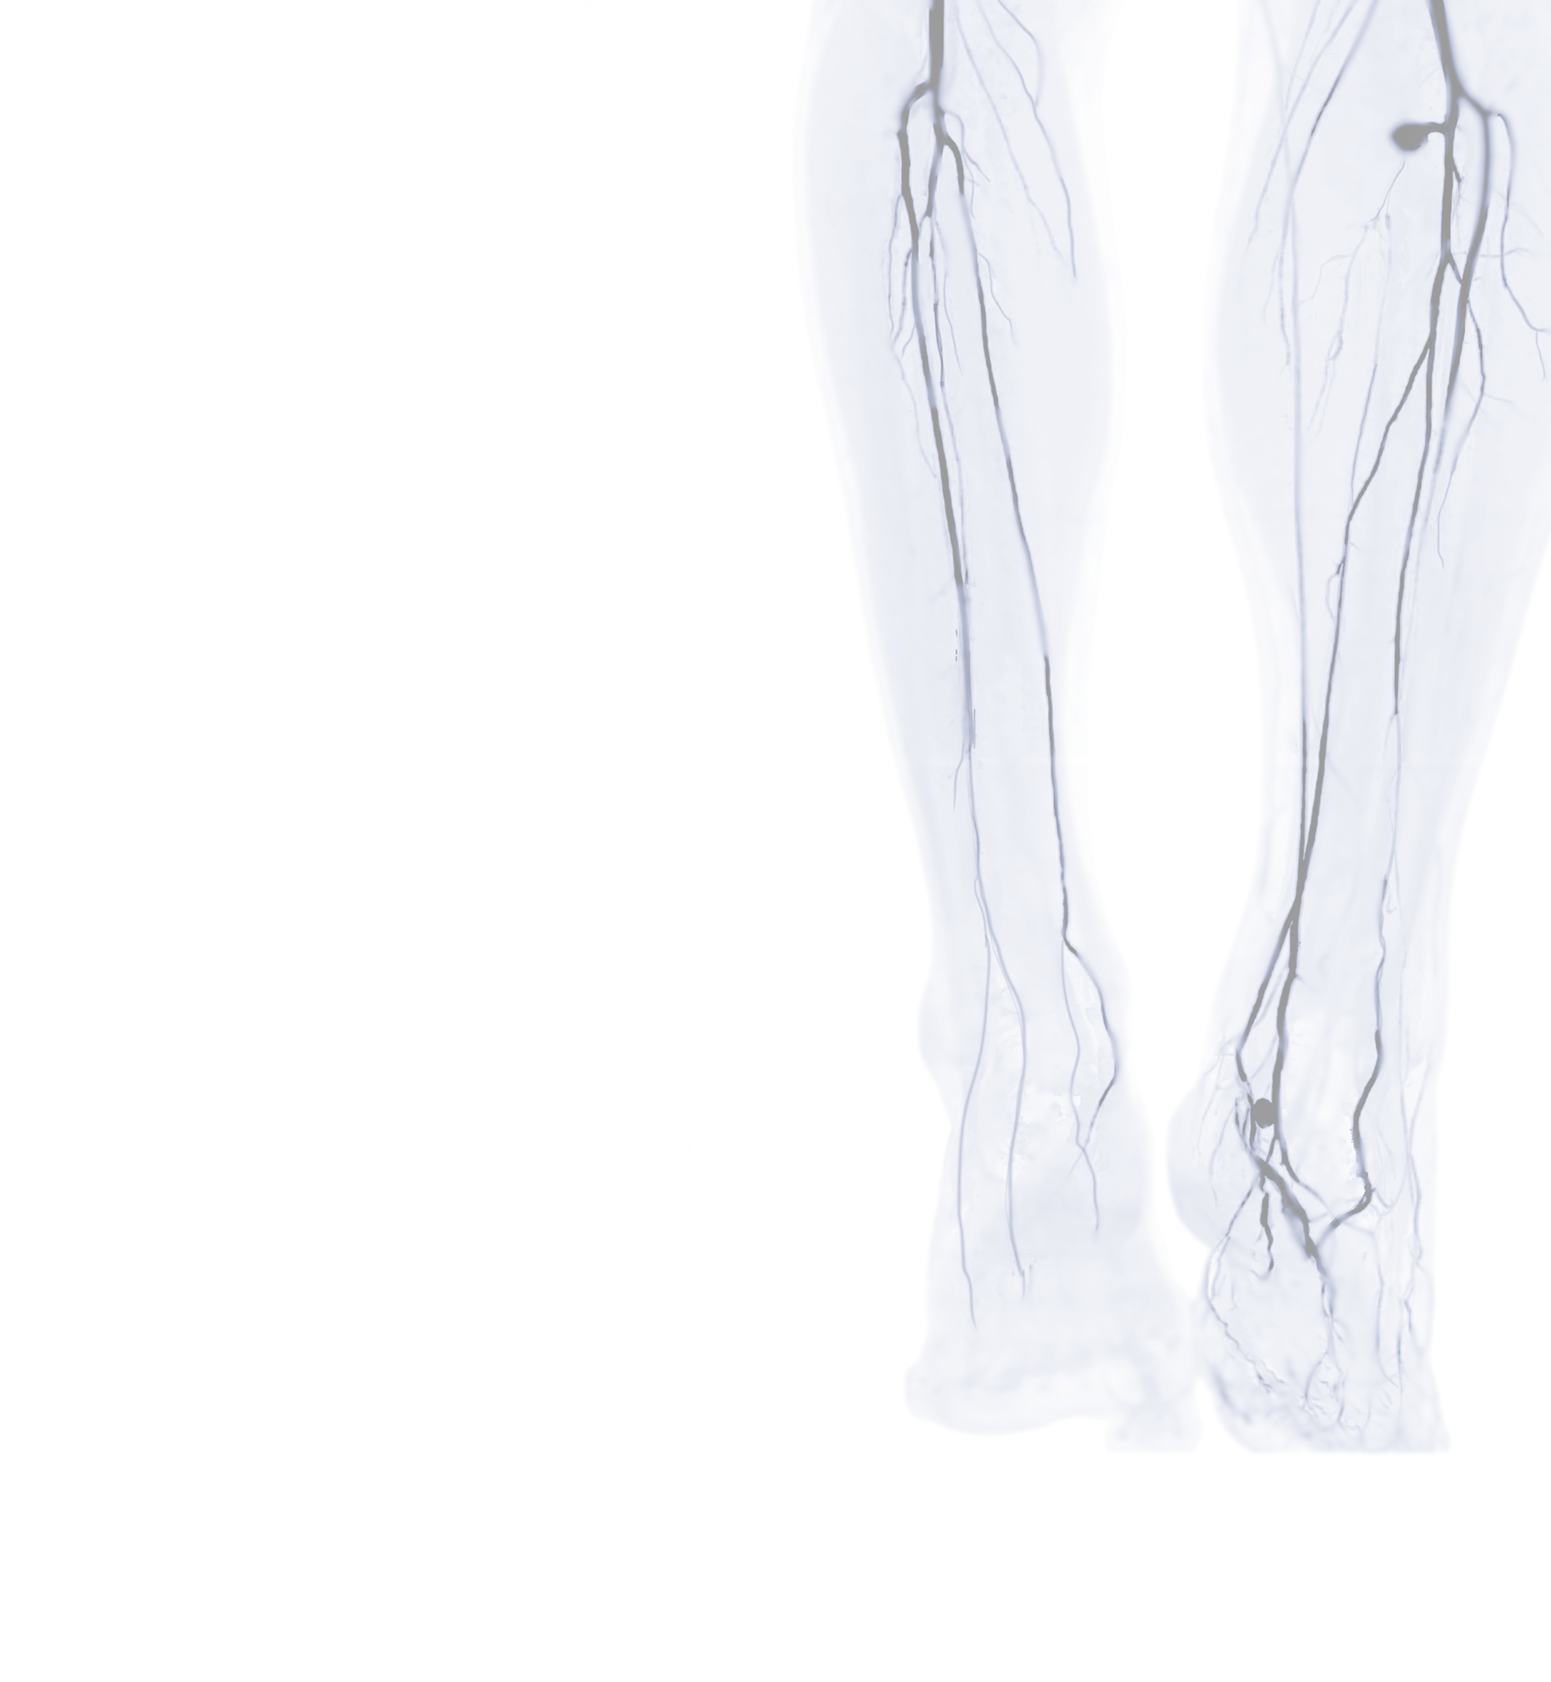

Peripheral angiography is the injection of contrast to evaluate for peripheral arterial disease, or the narrowing of arteries in the arms and legs, along with indicated procedures such as angioplasty or stenting to open the blockages.

This procedure is done while you are awake; however, you will be given medicine to help you relax during the procedure. Using local anesthesia or numbing medicine, a needle is placed in your groin or arm and a small tube is advanced through your artery. Contrast is then injected through that tube and X-Ray pictures are taken.

Angioplasty is when a tiny balloon is inserted through the tube into the area of the blockage. The balloon is then inflated for short intervals to compress the plaque or fatty deposits against the artery wall in order to open the artery to allow more blood flow.

Stents are sometimes used to help keep the artery open after angioplasty. Stents are tiny wire tubes on a balloon. Similar to angioplasties, the balloon and stent are inflated over the area of the blockage. The balloon is inflated at short intervals. When the balloon is deflated and removed, the stent stays in place at the area of the blockage.